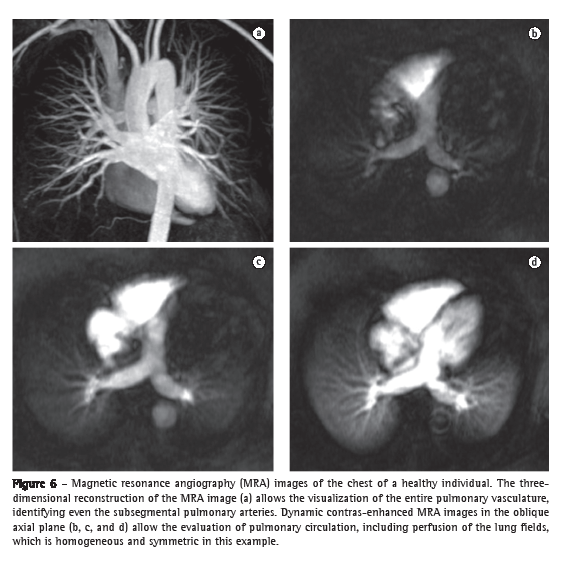

By means of the new MRA techniques, principally the use of gadolinium-enhanced 3D GE sequences, it is now possible to identify even the fourth-order subsegmental pulmonary arteries of a normal lung. This technique allows the acquisition of images of high temporal resolution every 1.0-1.5 s, and these images can also be used to study lung parenchyma perfusion (Figure 6).(40) The GE sequences that show blood flow with high signal intensity, also known as bright blood sequences (balanced GE sequences, cine MRI, and cine phase-contrast MRI) allow the evaluation of the large blood vessels of the thorax without the need for contrast use, as well as allowing the dynamic evaluation of and flow measurement in the pulmonary arteries and aorta, thereby providing functional information for use in morphological studies.(41)